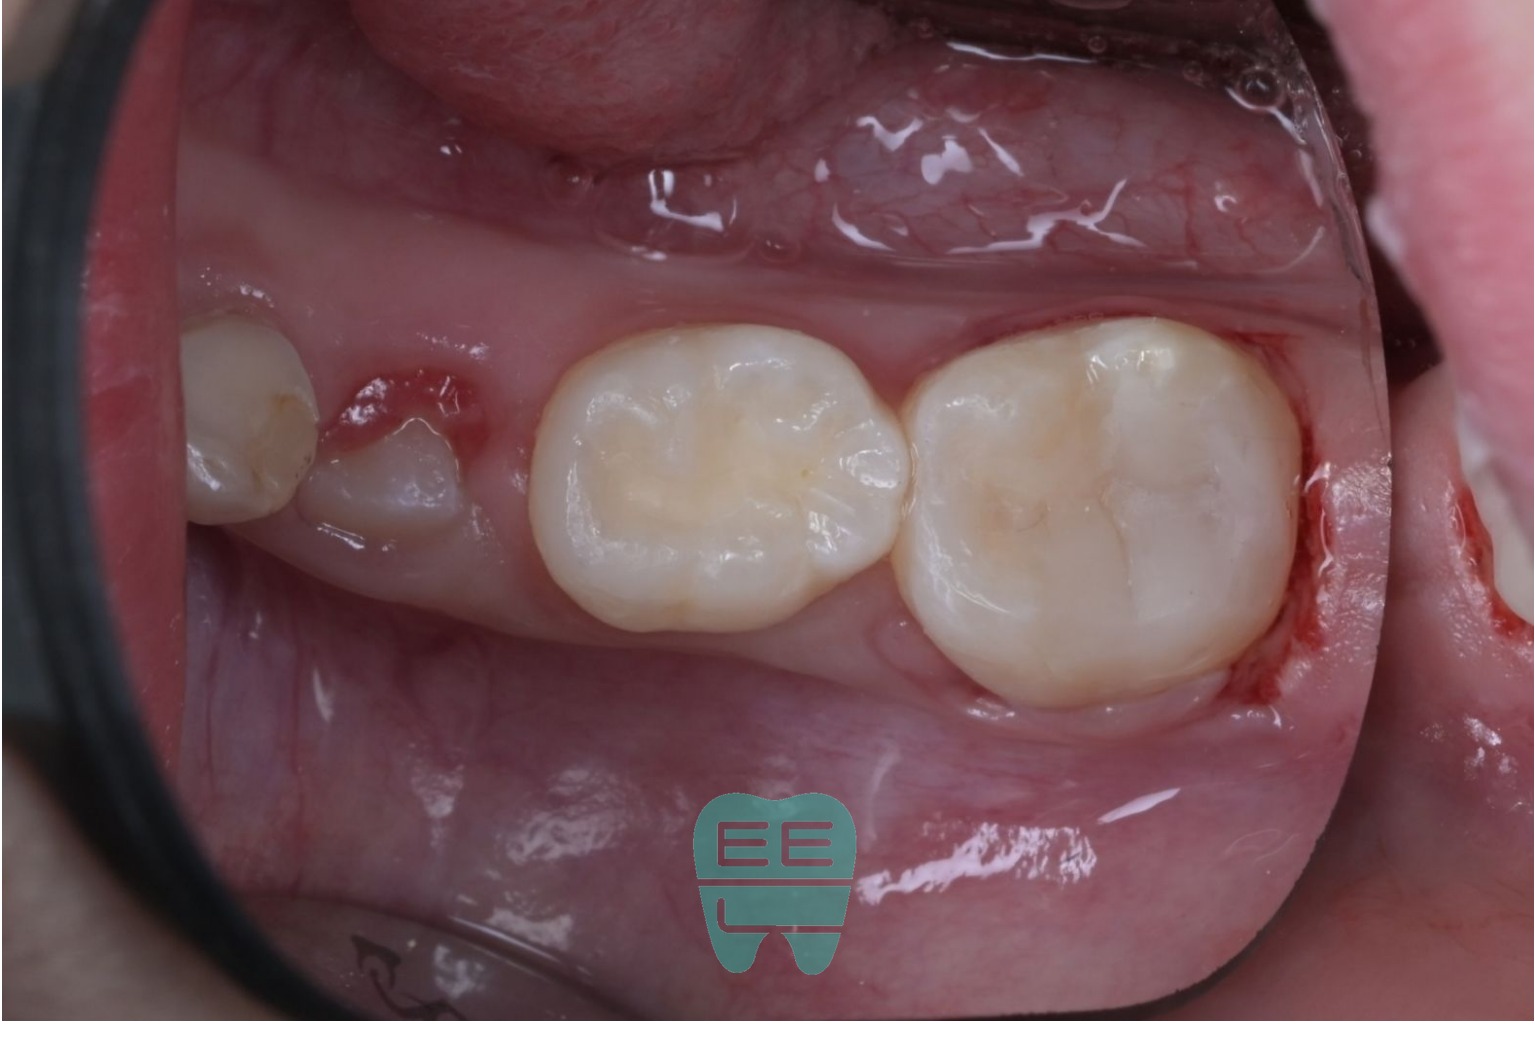

4. 러버댐 장착: 충치 치료 성공의 핵심

충치 치료의 성패는 결국 얼마나 완벽한 방습을 하느냐에 달려있습니다. 레이저로 잇몸을 적절히 다듬어 치아 경계를 확보한 뒤, 러버댐을 장착했습니다.

러버댐이 있어야 침과 혈액이 치료 부위에 오염되지 않고, 접착제가 최대의 성능을 발휘할 수 있습니다. 특히 소아 환자에서는 침 조절이 어렵기 때문에 러버댐이 더욱 중요합니다.